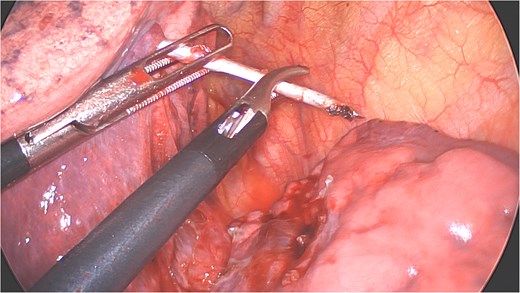

A clear minor pleural effusion and translucent scissural and para-aortic adhesions were visible. The adhesions of the pulmonary apex were released but no abnormality of the parietal pleura nor bone was visible. As the lung then collapsed, the pin became spontaneously visible protruding in the main fissure. As expected, the proximal part was in segment 2 and the distal half inside the apical segment of the lower lobe (S6) but it did not protrude outside of the parenchyma on either side (Fig. 4). The K-wire was easily removed by gently pushing back the parenchyma towards both extremities (Fig. 5). The pin seemed to be surrounded by a fine membrane that was coagulated at the visceral pleural entry point.

Extraction of the K-wire by pushing the parenchyma towards both extremities.